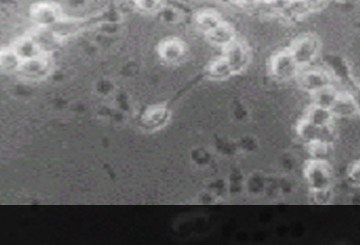

봉독투여 후 염증세포 감소